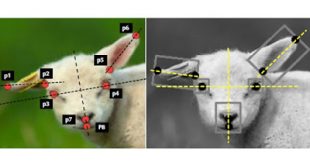

ΠερισσότεραΣύστημα τεχνητής νοημοσύνης κάνει διάγνωση του πόνου σε ζώα

Ερευνητές στη Βρετανία δημιούργησαν το πρώτο σύστημα τεχνητής νοημοσύνης που είναι ικανό να ανιχνεύσει το επίπεδο του πόνου σε πρόβατα. Το σύστημα, το οποίο μπορεί επίσης να εφαρμοσθεί σε άλογα, λαγούς, τρωκτικά κ.α., θα βοηθήσει μελλοντικά τους κτηνίατρους στην έγκαιρη διάγνωση και θεραπεία κοινών παθήσεων σε διάφορα ζώα. Το σύστημα …